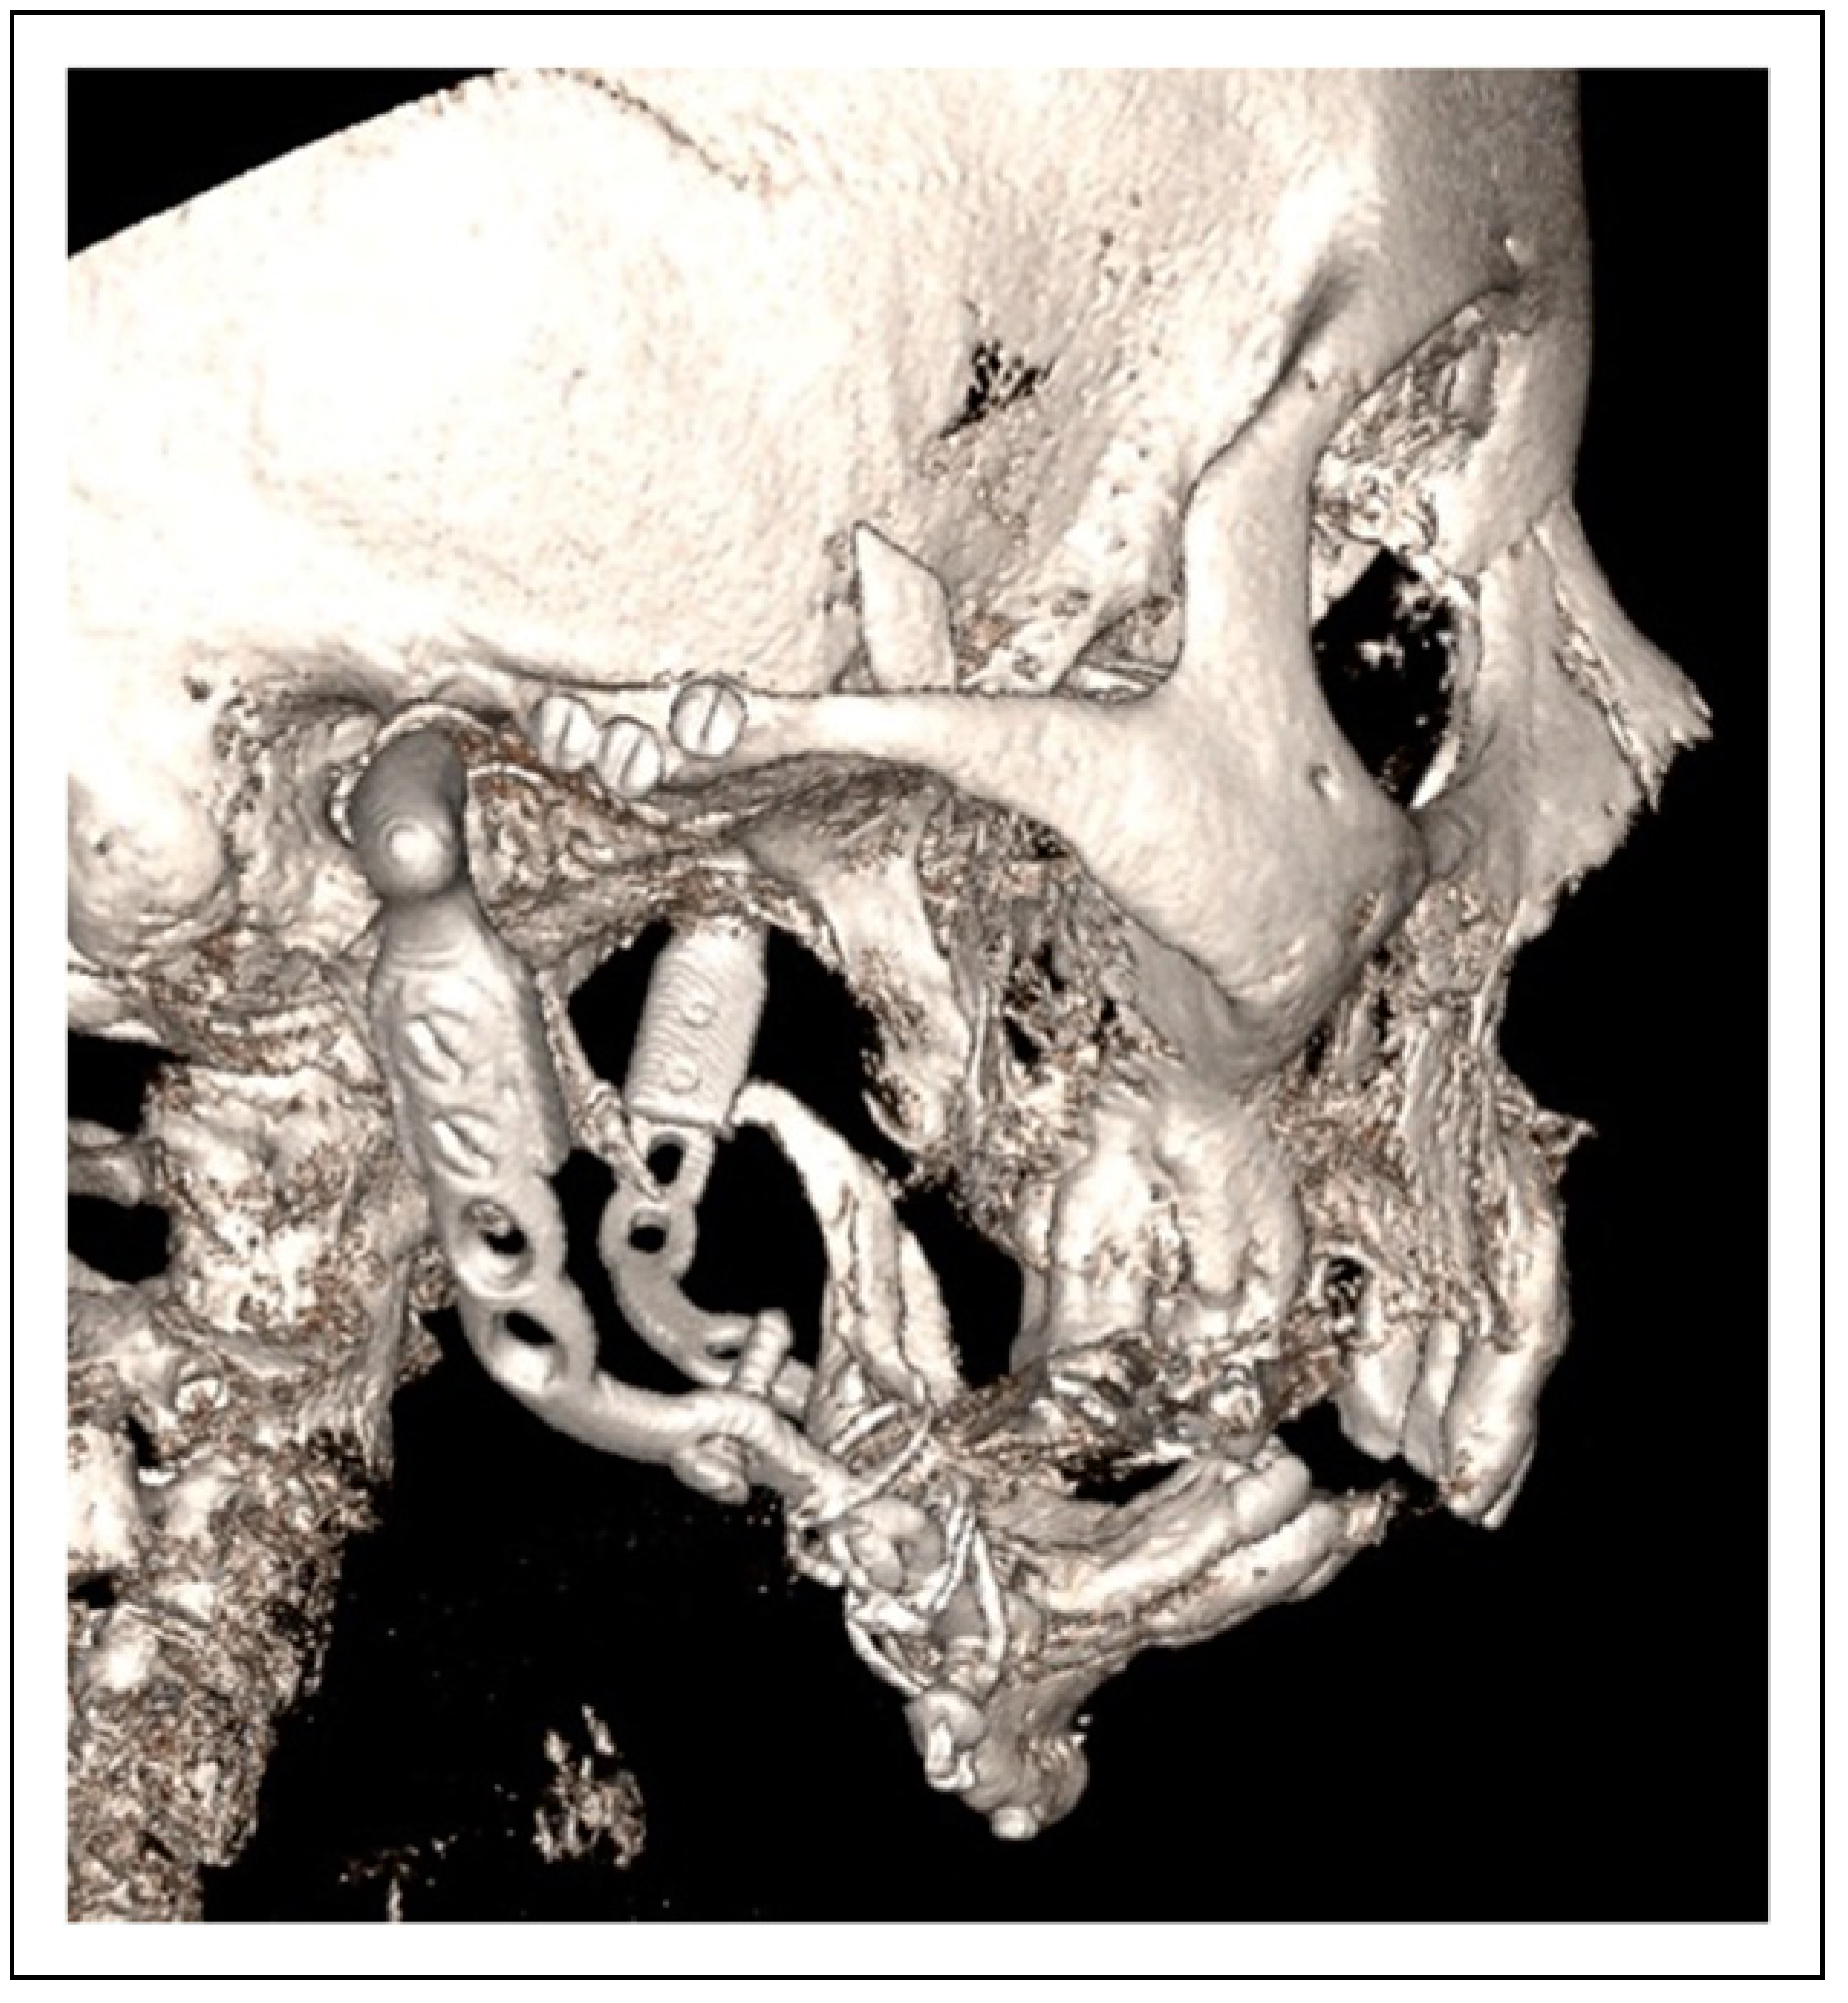

Bilateral TMJ Replacement With Complete Replacement of the Mandible, Patient 8